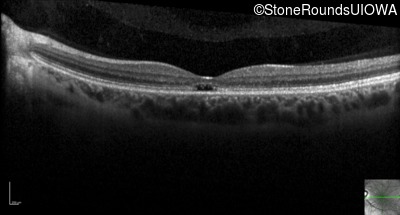

Optical Coherence Tomography - Right - 20/20 -1

Exemplar / OCT Stack